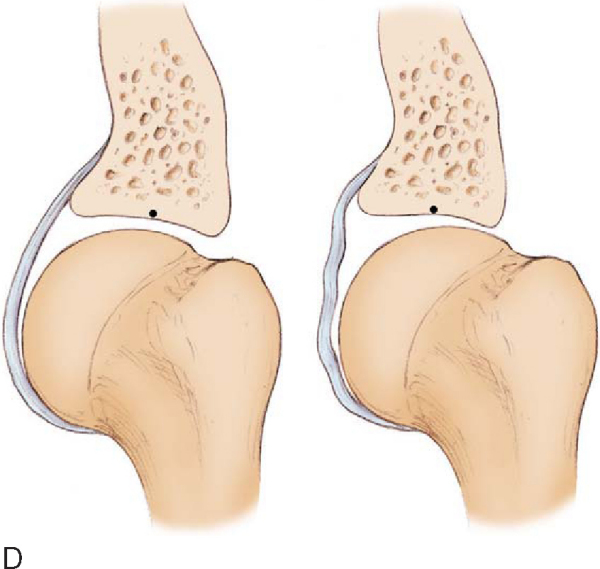

). This shift allows clearance of the greater tuberosity over the posterosuperior glenoid rim, enabling hyperexternal rotation (unlike normal internal impingement). In addition, the posterosuperior shift causes a relaxation of the anterior capsular structures, which manifests as anterior “pseudolaxity” and allows even further hyperexternal rotation around the new glenohumeral rotation point (

Fig. 10-1D

).